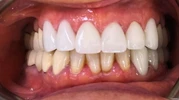

Fotoğraflar